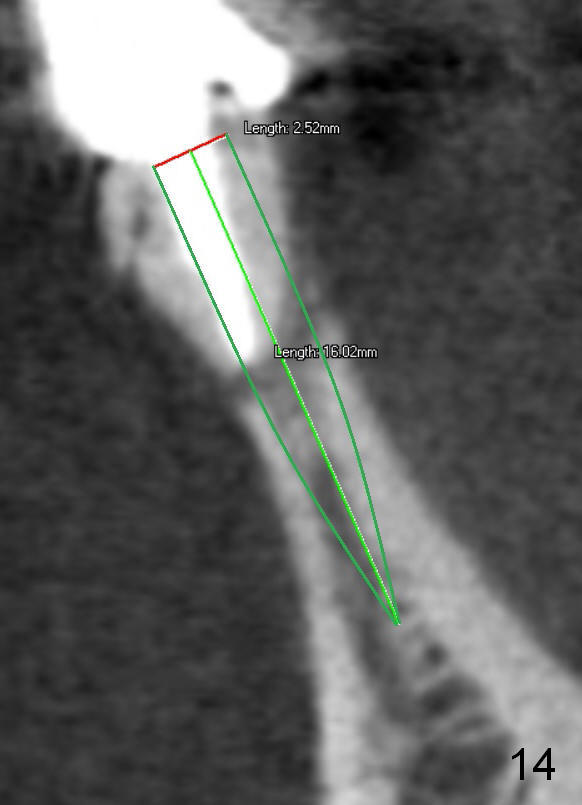

Fig.7 shows these two one piece implants immediately prior to cementation of the FPD (Fig.8). They are much more parallel to each other after prep, as compared to Fig.6. Fig.9 shows apparent bone growth around #24 implant (at the crest) 6,9 months post cementation and surgery, respectively. Orthodontic treatment will incorporate the fixed partial denture. Fig.10 shows that bone grows coronally (arrow) to cover 3 threads (from #6 thread to #3) at the site of #24 one year after functioning. There is mild buccal gingival infection involving #26 retainer. Preop CBCT is reviewed to determine whether it is related to potential thread exposure. It appears that at the sites of #24 (Fig.13,14) and 26 (Fig.11,12), 2.5 mm implant is more appropriate for the narrow ridge than 3.0 mm one. In fact, periimplantitis develops at #26 two years of absence of perio maintenance (because of atrial fibrillation with blood thinner; Fig.15, 3 years 7 months post cementation). Periimplantitis persists 4.5 months later. Although water pik is purchased, it is not used often because of low blowing force. If needed, remove the FPD atraumatically. Unwind the implant, clean the coronal threads with Titanium brush or remove the exposed threads and replant the implant with bone graft.